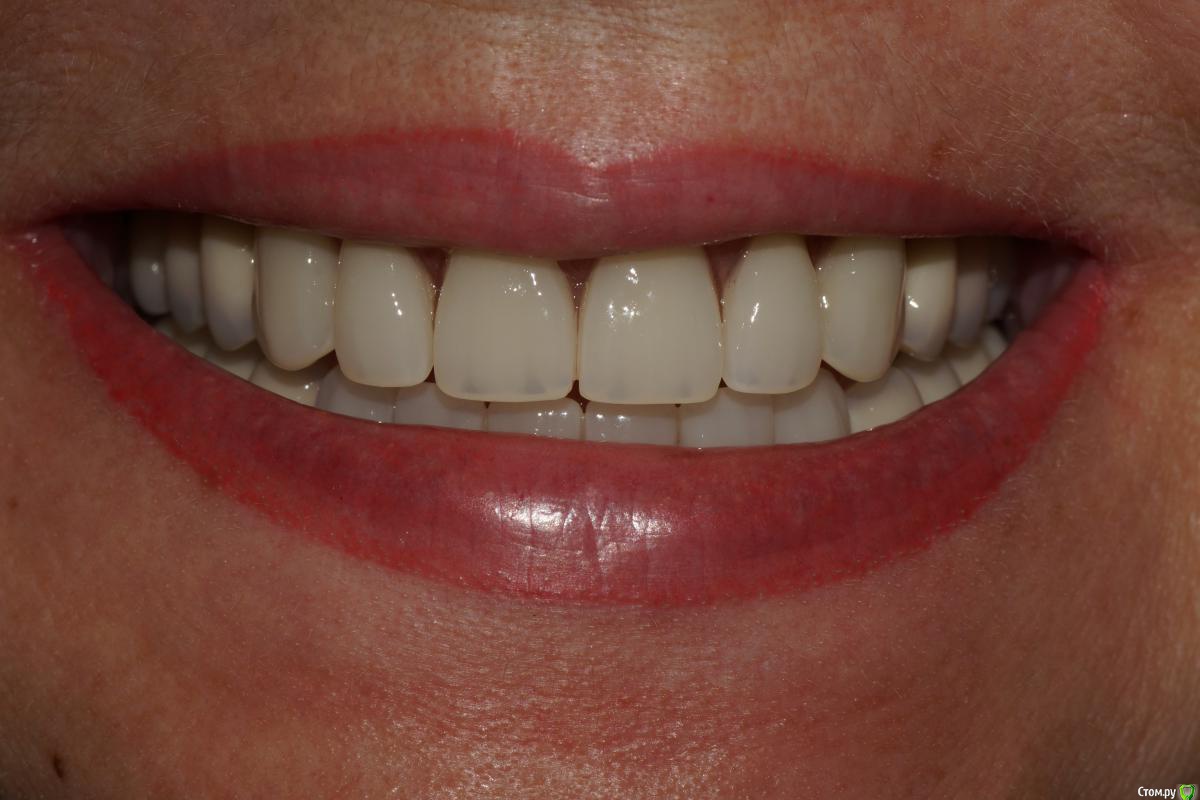

togrul Опубликовано 24 ноября, 2016 Автор Поделиться Опубликовано 24 ноября, 2016 Фото улыбки. 5 Ссылка на комментарий

stomalolog Опубликовано 25 ноября, 2016 Поделиться Опубликовано 25 ноября, 2016 Фото улыбки.Красиво, но немного молодые зубы для пациентки? 1 Ссылка на комментарий

togrul Опубликовано 25 ноября, 2016 Автор Поделиться Опубликовано 25 ноября, 2016 Красиво, но немного молодые зубы для пациентки?Спасибо. пациентка сама захотела форму и цвет) Ссылка на комментарий